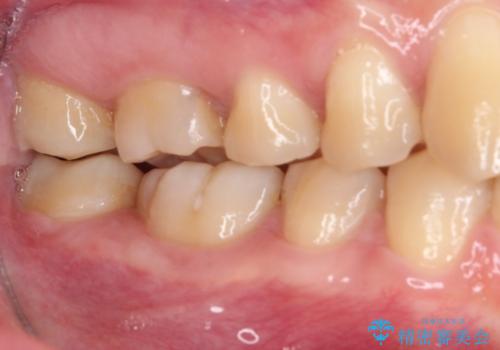

- 矯正治療後に目立つ銀歯を白くしたいとのことで来院された患者様です。

右下の銀の詰め物は、外してむし歯を除去した後、セラミックインレーにて修復することとしました。

左上の銀歯は、銀歯の下に金属の土台が入っているため、その土台を除去し、ファイバーコアにやり替えて、オールセラミッククラウンにて補綴することとしました。

適合の良いセラミック治療は、むし歯再発のリスクが低いです。

目立つ銀歯がなくなり、患者様は大変満足されました。